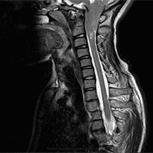

Patologia del Filum, frequente e sconosciuta